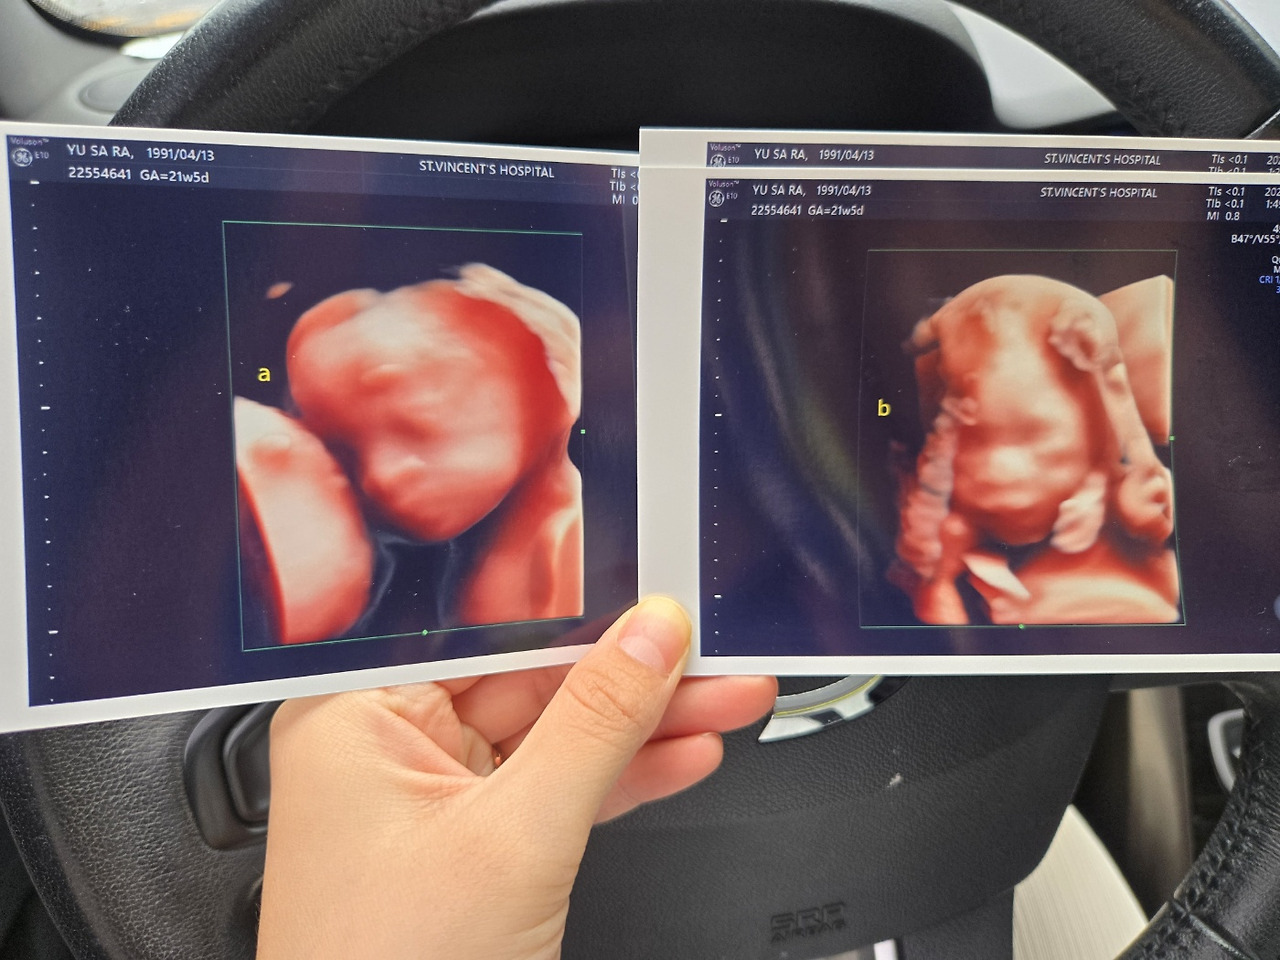

그 사이 나는 시험관 시술 2차만에 쌍둥이를 품었다. 배아 1개를 이식했는데 그 하나가 분열을 했고, 일란성 쌍둥이를 품게됐다. 이젠 나도 불행 끝 행복 시작이구나하는 생각에 정말 뛸듯이 기뻤다. 말로 형용할 수 없을만큼 행복했고 벅찼다.

임신과 동시에 고위험 산모가 되는 쌍둥이 임신은 항상 불안과 걱정을 달고 살게 했지만 매주 잘 커가는 쌍둥이들 덕분에 늘 행복했다. 남편은 물론 가족들, 친구들 심지어 동네 슈퍼 사장님까지도 나를 공주 대접해주며 온 마음으로 축하해주었다.